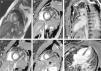

After rhythm stability was achieved, the etiological study was completed by performing cardiac magnetic resonance imaging, which was normal (Figure 3). Reassessment of the ECG tracings showed that all episodes of PVT were preceded by PVCs with no compensatory pause (absence of long R-R interval), followed by a short-coupling PVC (280–290 ms) (Figures 2B and 4). At this point, taking into account the patient's clinical history and complementary tests, a diagnosis of short-coupled variant torsade de pointes was established. Amiodarone was suspended and verapamil was started (120 mg twice daily). A cardioverter-defibrillator was also implanted with permanent atrial pacing. Genetic study was performed.